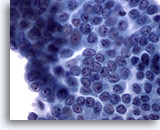

Positief voor maligniteit

Bij de monsters in deze categorie geldat dat bij resectie in bijna 100% van de gevallen een maligniteit wordt gevonden. Papillair carcinoom is de meest voorkomende maligniteit van de schildklier en heeft specifieke nucleaire kenmerken die eenvoudig zijn vast te stellen bij cytologische monsters. Andere maligniteiten waarvan de diagnose zeer nauwkeurig kan worden vastgesteld op basis van cytologie, zijn onder andere medullaire carcinomen, lymfomen, en metastatische carcinomen. Papillair carcinoom wordt gekenmerkt op ThinPrep door lagen en papillaire clusters van opeengepakte cellen met kernvergroting en molding, poederige chromatine, onregelmatige kerncelmembranen (met name kerngroeven en intranucleaire cytoplasmische inclusies), en kleine maar prominente en vaak eosinofiele nucleoli.[7] Daarentegen wordt medullair carcinoom gekenmerkt door geïsoleerde monomorfe plasmacytoïde cellen, die een hoge kern/cytoplasma-ratio hebben, excentrische kernen en grofkorrelige chromatine met of zonder een prominente nucleolus. Kleine, onopvallende granulen vullen het cytoplasma. Soms lijken de cellen spoelvormig, maar vertonen ze dezelfde nucleaire kenmerken. Lymfomen en metastatische carcinomen van de schildklier komen veel minder vaak voor. Hun cytologische kenmerken hangen af van het type en de plaats van oorsprong.